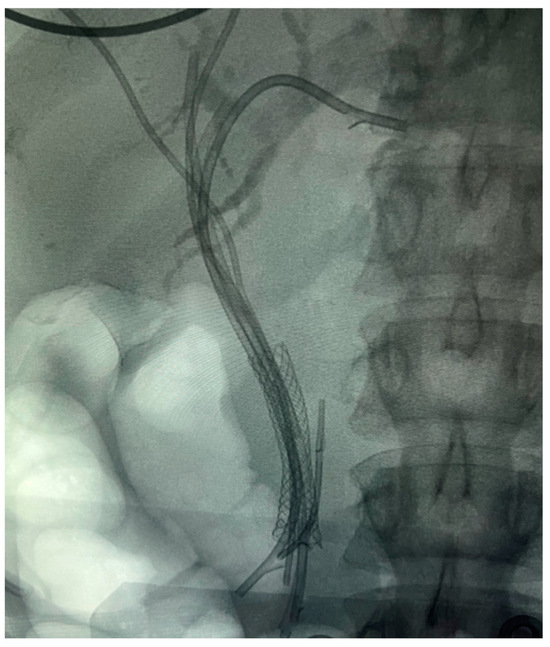

7.1.1. Endoscopic Biliary Stenting (EBS)

7.1.3. EUS-Guided Biliary Drainage (EUS-BD)